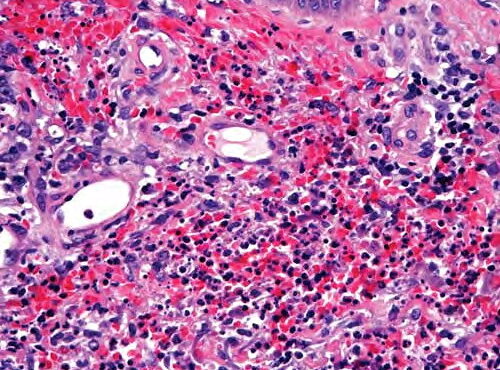

Read MoreNeutrophilic dermatosis= الجلاد بالمعتدلات Sweets Syndrome and Sweets Like Neutrophilic Dermatosis Dr. R. D. Sweet described in 1964 a disease process, which he termed “acute febrile neutrophilic dermatosis,” that was characterized by abrupt onset of fever, leukocytosis, and erythematous plaques infiltrated by neutrophils . This condition typically occurs in middle-aged women after nonspecific infections of […]